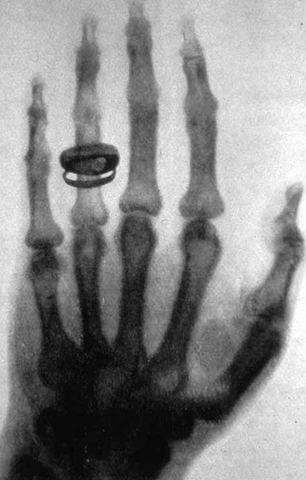

• Invención de los Rayos X

Invención de los Rayos X

Descubrimiento de los rayos X en 1895. A finales del siglo XIX, en 1895, Wilhelm Conrad Röntgen (1845-1923), científico alemán de la Universidad de Würzburg, descubrió una radiación (de origen desconocido en aquel momento, y de ahí su nombre de rayos X) que tenía la propiedad de penetrar los cuerpos opacos.